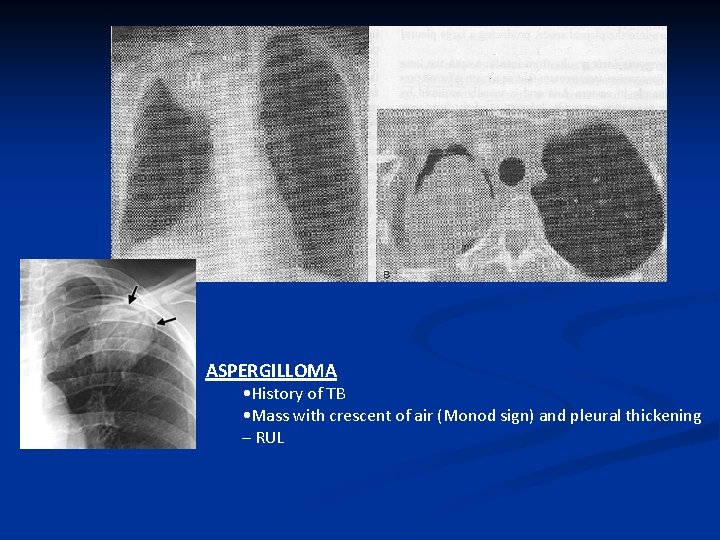

ASPERGILLOMA • History of TB • Mass with crescent of air (Monod sign) and pleural thickening – RUL